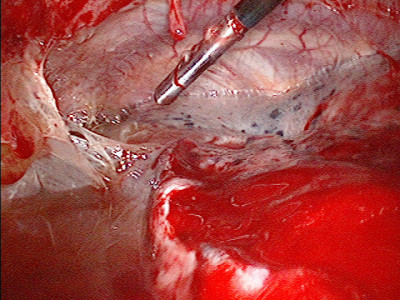

Absceso pleural apical posterior